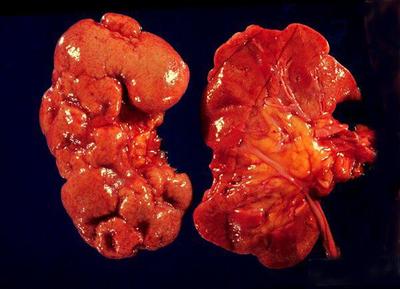

Which of these pictures is pyelonephritis?